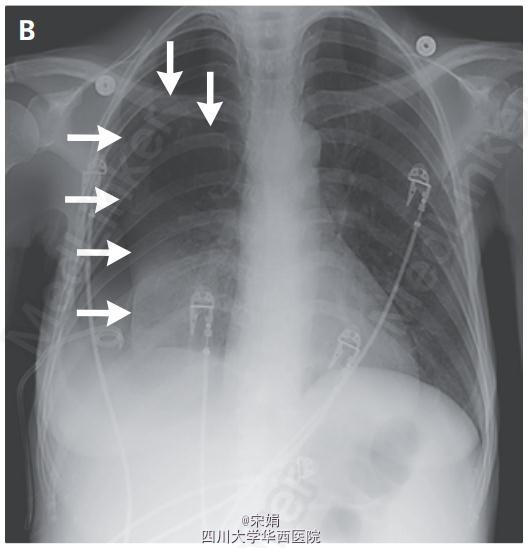

患者为46岁女性,呼吸困难就诊,患者因终末期肝病出现复发性肝性胸水,需要反复胸腔穿刺。胸部检查发现右肺无呼吸音。胸片显示液气胸(图A,箭头显示气胸,星号显示液胸)。遂留置猪尾导管引流胸腔积液,但气胸仍持续存在(图B,箭头)。